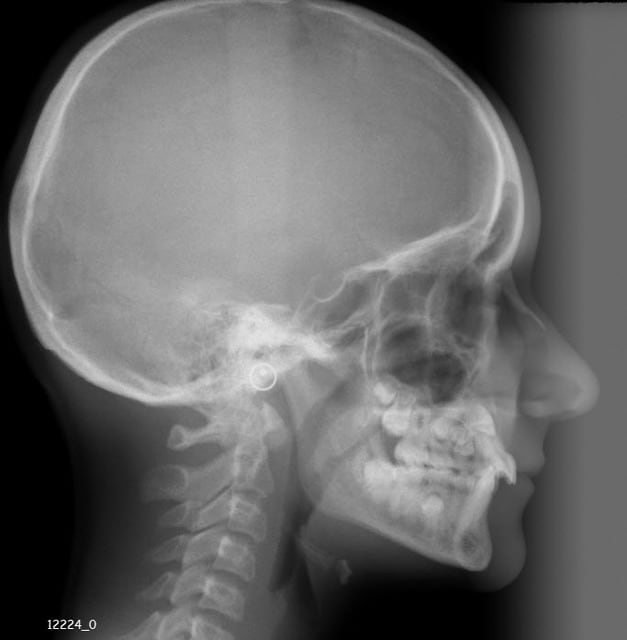

Jeune fille de 12 ans.

Il n'y a aucun élément caché, cette panoramique se suffisait à elle-même pour montrer toute la problématique du cas en trois points :

- 13 incluse.

- 23 incluse.

- 14 "un peu" penchée, sa racine passe au dessus de l'apex de la 53 et vient titiller la couronne de la 13.

À votre avis, au vu de la téléradio de profil, 13 et 23 sont-elles incluses en vestibulaire ou en palatin ?

Je rappelle que lorsque la canine incluse est vestibulaire elle paraît horizontale sur la radio de profil alors qu'elle est plus verticale dans le cas d'une position palatine.